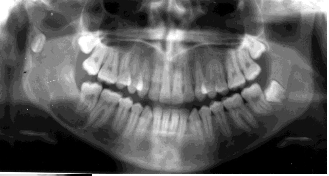

What’s an ameloblastoma?

May mimic other radiolucencies.

What’s a unicystic ameloblastoma?

Account for ~15% of Ameloblastoma. Equal distribution between maxilla and mandible. Usually unilocular associated with the crown of an un erupted tooth peak age 35 years.